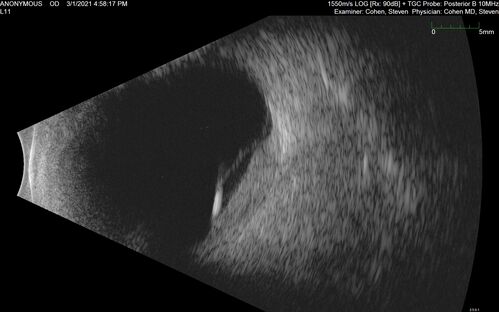

Bilateral Choroidal Tumors - Metastatic Breast Cancer

51 year old female.  First 3 sets of images show lesions growing despite systemic chemotherapy.  She eventually had external beam radiation x 15 sessions and the tumors shrunk in the last two sets of images